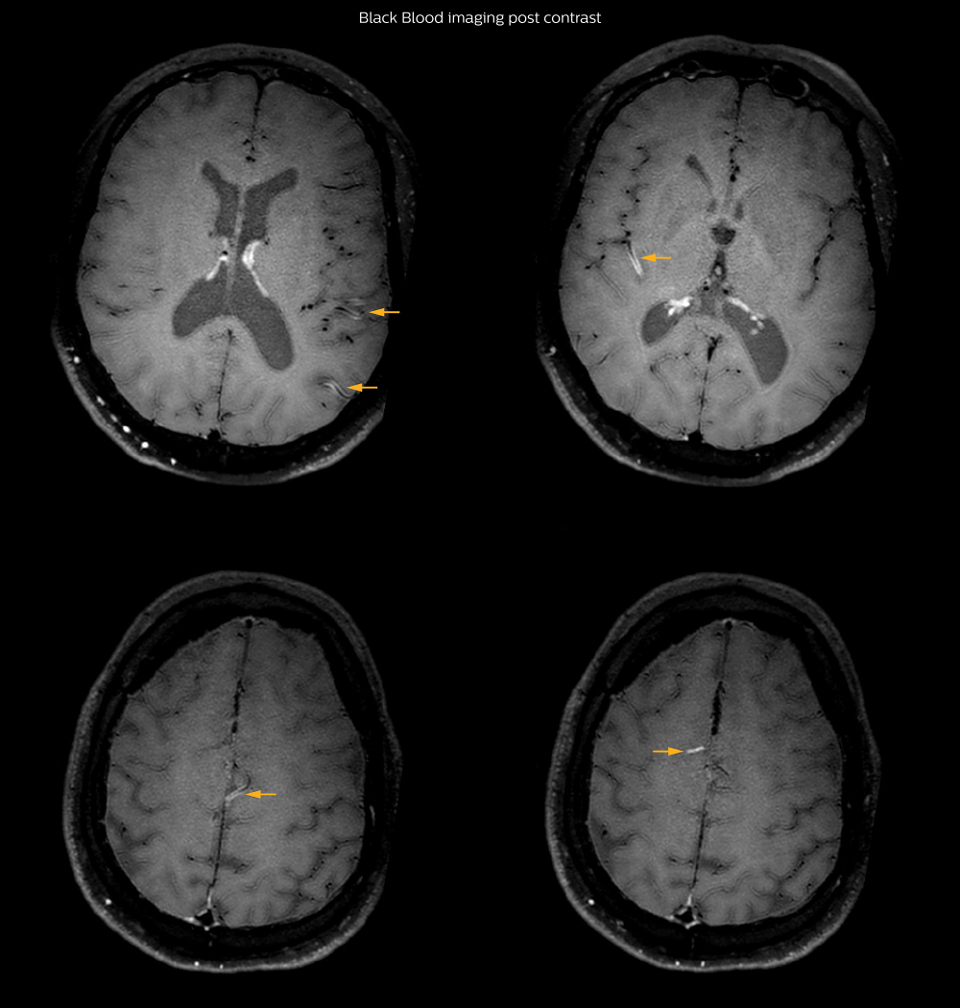

On FLAIR images we can see some nonspecific high signal abnormalities in frontal white matter bilaterally. On DWI we can see acute ischemic lesions which appear with high signal intensity. Arrows show vessel wall enhancement which appears concentric and homogeneous in different cerebral territories.

On the routine MR sequences that we did, we could see acute ischemic lesions. We see them very well on the diffusion images, where acute ischemic lesions usually appear with high signal intensity and restricted diffusion. However, the etiology of these lesions cannot be derived from these images. An area of restricted diffusion was seen in the anterior cerebral artery territory and we concluded it was an ischemic lesion. On MR angiography we can just see if there is stenosis or vessel occlusion, but it does not provide us information on the etiology of this kind of lesion. So, we decided to perform Black Blood imaging. The presence and the pattern of vessel wall enhancement on Black Blood imaging, can help us to determine the etiology of the lesion. differentiate vasculitis from other causes of vasculopathy, such as atherosclerosis, with a high specificity [1-3]. In an atherosclerotic lesion, vessel wall thickening and enhancement are usually eccentric, while in vasculitis the wall thickening and enhancement are usually concentric, homogenous, and in a long portion of the vessel. of patients whenever their treatment is installed in order to determine the efficacy of a particular treatment. In this case the Black Blood imaging helped us to suggest the diagnosis of HIV-related brain vasculitis.

had, such as glucose intolerance, arterial hypertension and hypocholesteremia, his lesions could be atherosclerotic lesions or vasculitis, conditions which require different treatment. Especially in this patient with HIV infection causing the vasculitis, treatment of the two conditions is different. The results of MRI with Black Blood imaging, helped to choose the preferred treatment for this patient, which was based on antiviral medication rather than an antiaggregant or anticoagulation treatment which is usually given to patients with risk of ischemia based on atherosclerotic lesions. One month after beginning the antiviral treatment, the same MRI examination was repeated and again 8 months after the beginning of treatment. On follow-up images, we see the enhancements have almost disappeared. So in case of this patient, the MRI exam with Black Blood imaging helped us to give the patient the appropriate treatment and also allowed us to noninvasively confirm the treatment response.

With the multiple cardiovascular risk factors this patient